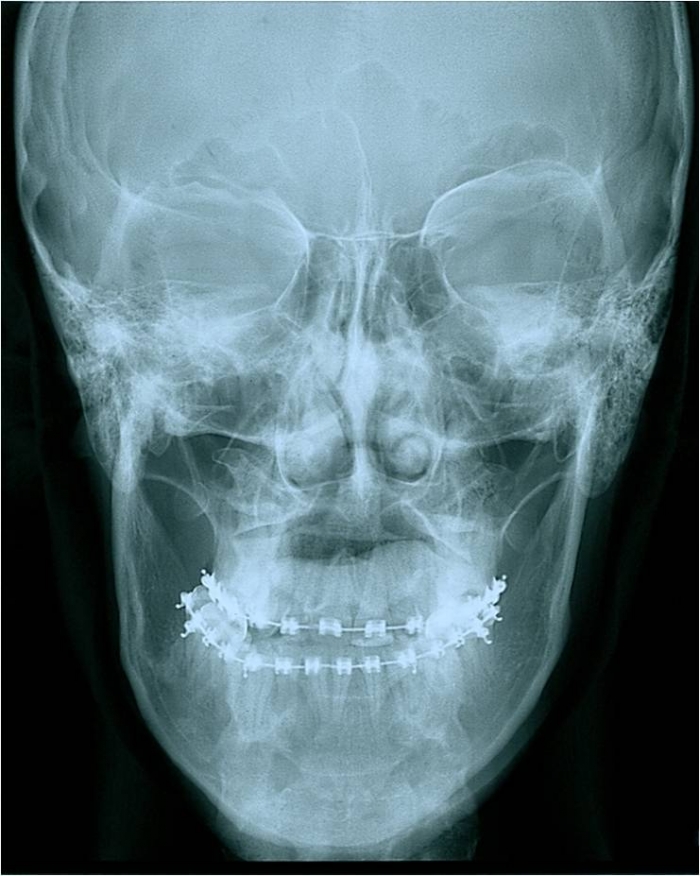

Telerradiografia frontal após a cirurgia - Clínica Cliniface

Telerradiografia frontal após a cirurgia